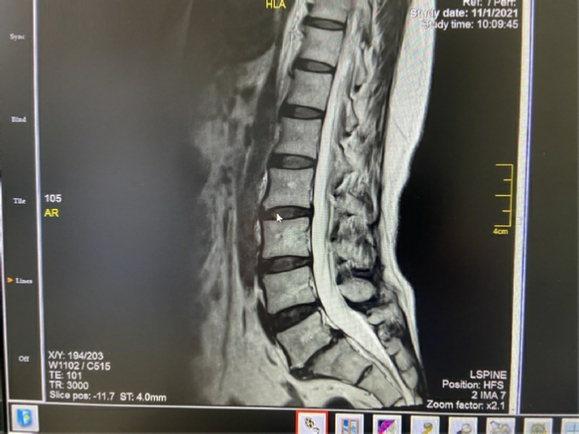

Στις δύο ανωτέρω εικόνες είναι εμφανής η έντονη εκφύλιση του μεσοσπονδυλίου δίσκου Ο5-

Αυτή η περίπτωση είναι ιδανική για διενέργεια πρόσθιας διασωματικής σπονδυλοδεσίας, η οποία και διενεργήθηκε με τη χρήση ευρέως κλωβού και μίξη αυτομοσχεύματος από το λαγόνιο (μέσω της ίδιας τομής) και DBM. Σταθεροποίηση με τρεις βίδες με πολύ καλή συγκράτηση και συμπίεση του κλωβού. Ακολουθούν οι μετεγχειρητικές ακτινογραφίες.